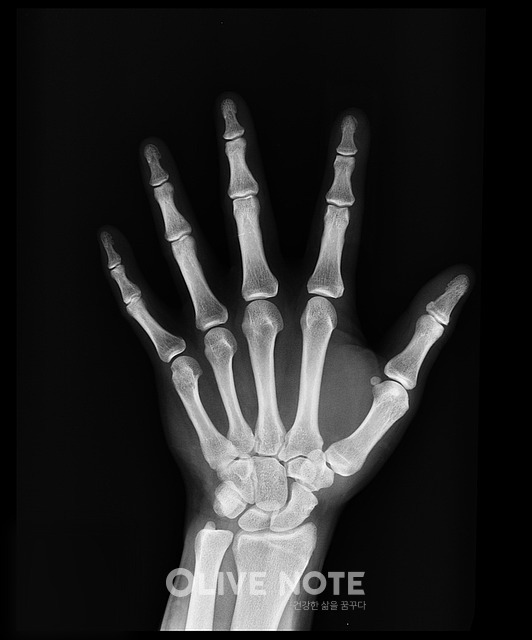

1054_2352_5820.jpg 성조숙증 여부를 확인하기 위해 왼쪽 손목 X레이 검사 등을 실시한다.

X레이 촬영이 가능한 소아과에선 대체로 성조숙증 검사가 가능하다. 우선 체중과 몸무게, 2차 성징 출현 정도 등에 대한 진찰 후 복강 내 질환에 대한 진찰과 안과적 진찰, 왼쪽 손목 X선 검사를 통해 골연령 검사를 한다. 이후 성조숙증이 의심된다면 혈액을 뽑아 호르몬 분비 자극 검사 등을 실시한다. 신체적인 고통이 따르는 검사는 없으며 비용은 검사 정도와 병원에 따라 5만~40만원 정도로 차이가 크다.